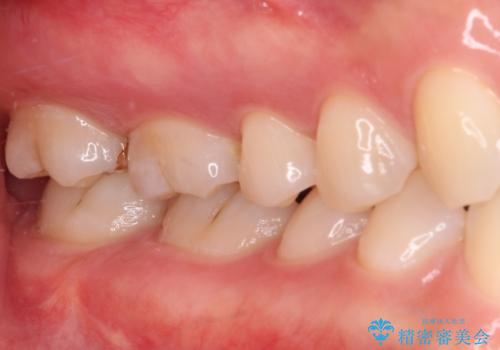

- 奥歯の銀歯と虫歯を気にして来院された患者様です。

下顎は口を開けたときに目立つためセラミックインレーに、上顎奥歯は機能面を優先してゴールドインレーにて修復治療を行うこととしました。

機能面を優先すると、PGAインレー(ゴールドインレー)による修復治療やPGAクラウンによる補綴治療が望ましいのですが、笑ったときに見えている銀歯がどうしても気なってしまうとのことで、目立ってしまう奥歯はセラミックインレーやセラミッククラウンを装着することとしました。

見た目を気にすることなくむし歯治療を行うことができ、患者様に大変満足していただきました。